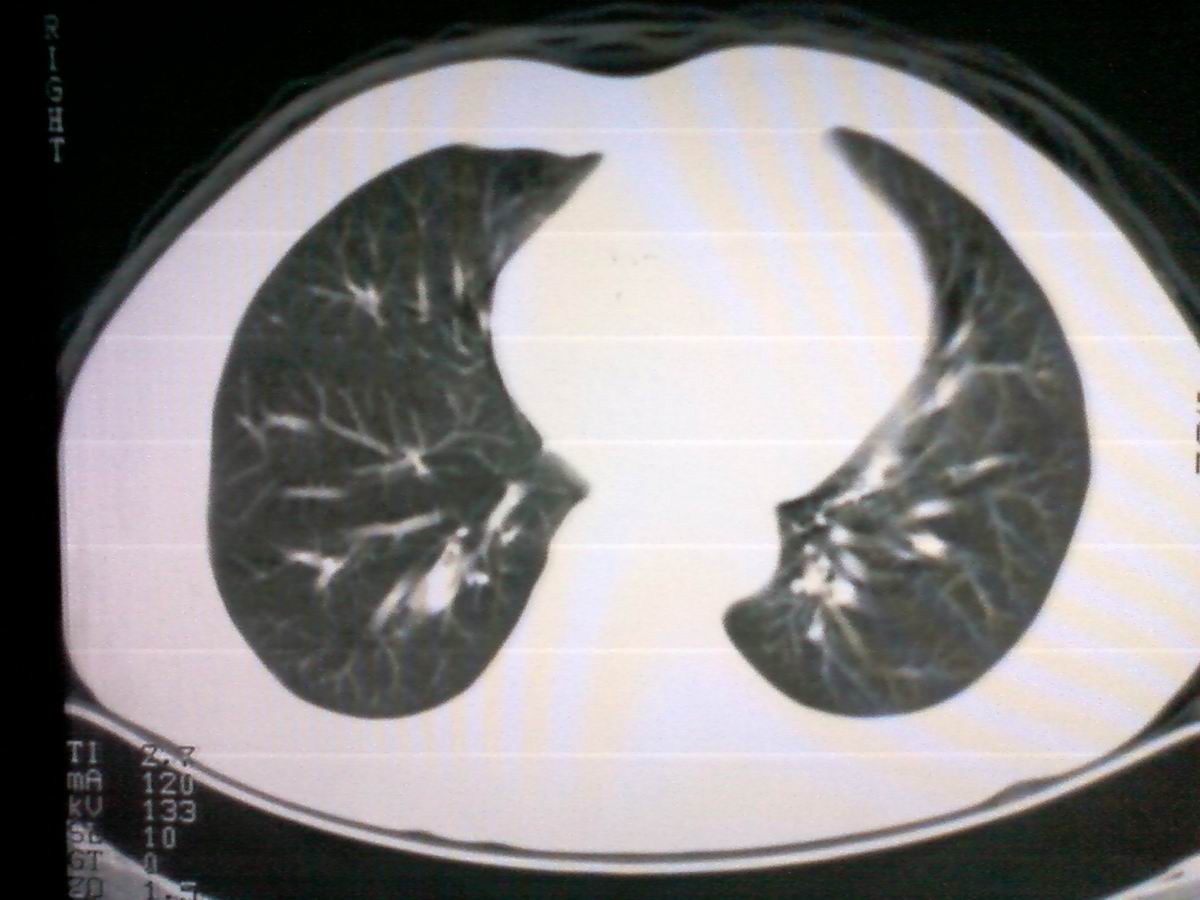

标题: CT25801:患者男性,65岁,临床提示双肺可闻及广泛罗音,看 [打印本页]

标题: CT25801:患者男性,65岁,临床提示双肺可闻及广泛罗音,看

仅见肺纹理影增重 纵膈淋巴结钙化